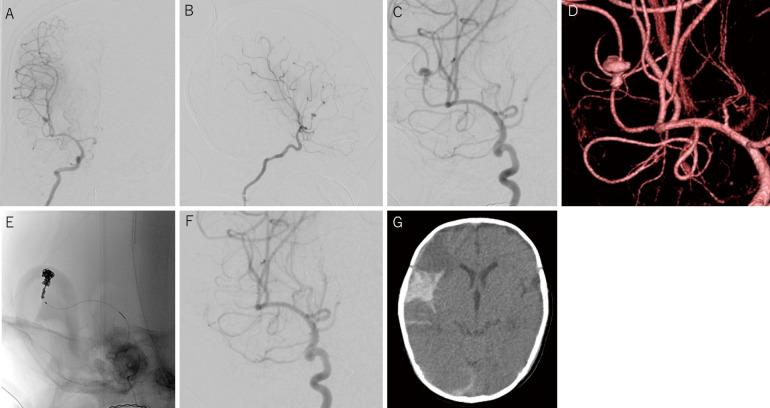

Intracranial aneurysms (IA) in infants are reportedly rare at 0.5% to 4.5% of all aneurysms. Furthermore, subarachnoid hemorrhage in infants younger than three months are even rarer as it has been reported in approximately 20 cases only till date. A 3-month-old infant with seizures and impaired consciousness was admitted to our hospital. Three-dimensional computed tomography angiography (3D-CTA) revealed a dissecting aneurysm with a maximum diameter of 13 mm in the right M2. Internal trapping using detachable coil were successfully performed, following which he was discharged without significant neurological deficit after one month of onset. Thus, we have reported a rare case of a large ruptured dissecting IA in a 3-month-old infant, in the right middle cerebral artery (MCA), successfully treated with an endovascular therapy, along with a literature review.

据报道,婴儿颅内动脉瘤(IA)罕见,占所有动脉瘤的0.5%至4.5%。此外,三个月以下婴儿的蛛网膜下腔出血更为罕见,迄今为止仅报道了约20例。一名3个月大、有癫痫发作和意识障碍的婴儿被收治入院。三维计算机断层血管造影(3D-CTA)显示右侧M2段有一个最大直径为13mm的夹层动脉瘤。成功进行了可脱卸弹簧圈的内套扎术,发病一个月后出院,无明显神经功能缺损。因此,我们报告了一例罕见的3个月大婴儿右侧大脑中动脉(MCA)大型破裂夹层IA病例,并成功接受了血管内治疗,同时进行了文献综述。